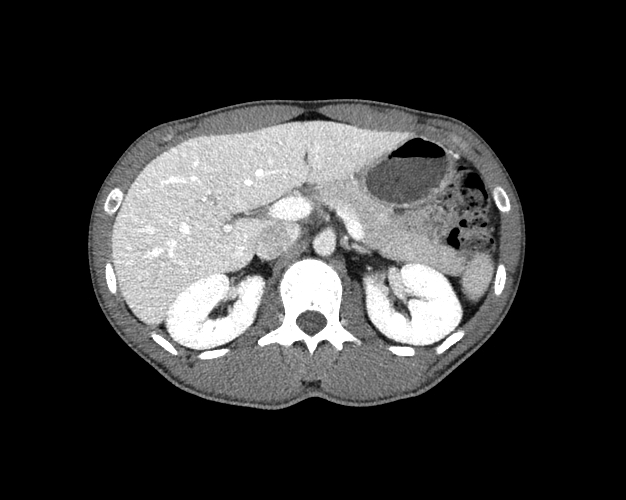

Body

Covers abdominal CT anatomy.